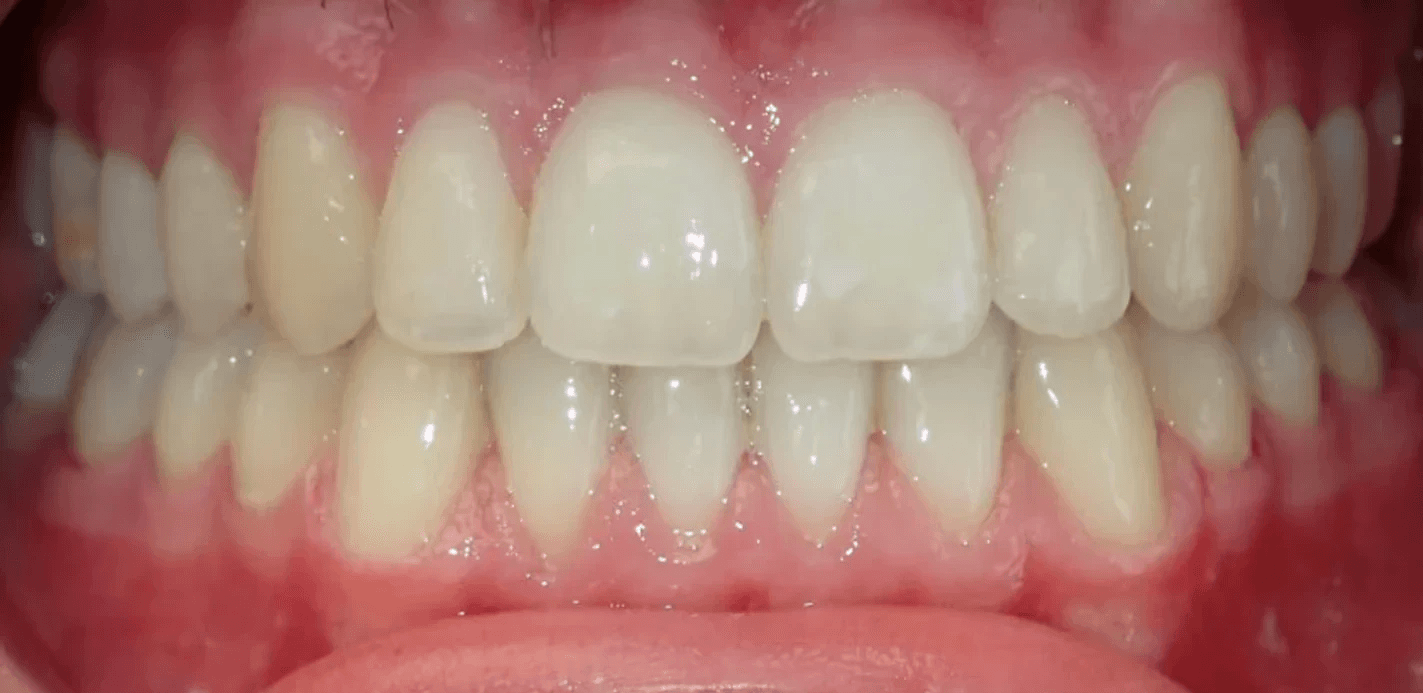

Final results

INTRAORAL